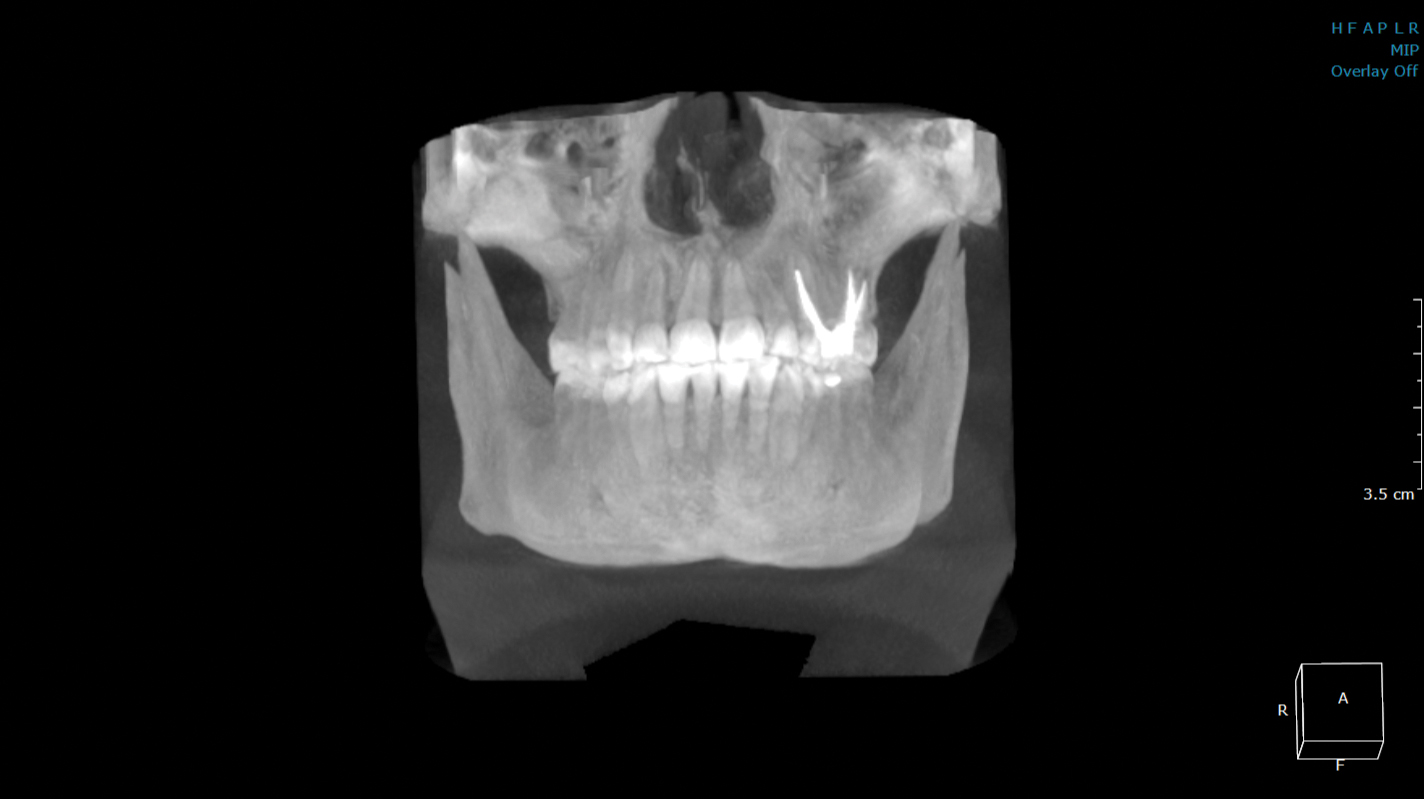

オルソパントモグラフ OP3D、ディゴラオプティメe、DTX Studio Clinic

当院には正確で安全な治療を行うための検査機器をとして、最新鋭の歯科用CTシステムを導入しております。このシステムは、低い被ばく線量(総合病院などの医科用CTの1/10以下)で、3次元データの情報を得ることができ、これまでのレントゲン検査の診断が難しかった部分の診断も行えます。これにより患者さんのへのわかりやすい説明と更なる治療成績の向上が見込めます。